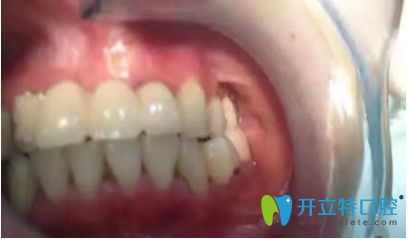

劉女士,33歲,據(jù)她描述,自己多年前在國(guó)內(nèi)一家口腔醫(yī)院做了烤瓷冠,但由于時(shí)間長(zhǎng)變的松動(dòng),考慮到自己還年輕,為了一步到位,她來(lái)韓國(guó)安特麗做了多顆牙種植。

在拆除烤瓷橋后,發(fā)現(xiàn)她的口內(nèi)埋伏牙,把埋伏牙拔除后,很順利的植入了種植體,完成了種植牙。

劉女士反饋,自己很后悔當(dāng)初做了烤瓷牙,她表示,自己對(duì)韓國(guó)的種植牙技術(shù)很認(rèn)可,所以來(lái)韓國(guó)做了種牙手術(shù)。